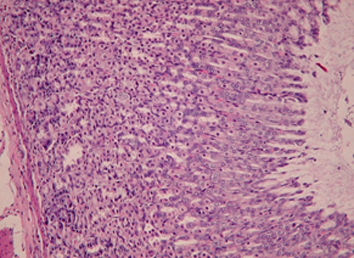

Результаты. Показано, что применение рифабутина в сочетании с аскорбигеном приводит к ослаблению повреждающего действия антибиотика на слизистую оболочку желудочно-кишечного тракта и ускорению процессов восстановления ее структуры, что клинически выражается в нормализации прироста массы тела животных. При комбинированном применении рифабутина с аскорбигеном уменьшается глубина цитопении, а количество лейкоцитов в периферической крови крыс восстанавливается быстрее. Признаки атрофии лимфоидной ткани селезенки отсутствуют. Введение аскорбигена до рифабутина оказывает протекторный эффект в отношении тканей почек и семенников.